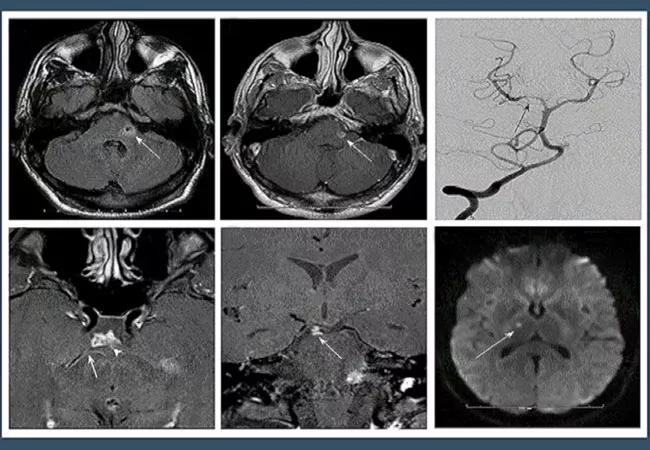

A series of brain MRI images used to help diagnose CNS vasculitis

A 32-year-old male presented to the emergency department with left facial numbness/drooping, dizziness and double vision. He has a history of chronic migraine since adolescence, and reports that they have been worsening in the last 6 months. He also has a several-month history of episodic dizziness with associated diplopia and left facial numbness/weakness for the past 6 months. Five months prior to presentation, the patient had been evaluated at another hospital system. Brain MRI at that time revealed a small infarct, for which he was treated with aspirin.

Brain MRI on admission to Cleveland Clinic revealed a new subacute left cerebellar infarct. Watch the video below, with Rula Hajj-Al, MD, to find out the next step in the differential diagnosis.